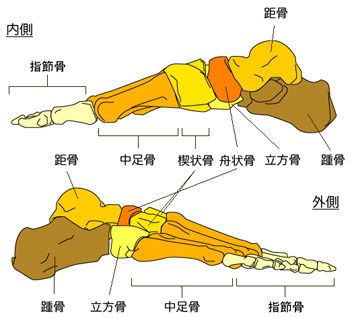

足関節の解剖について

代表的な靭帯損傷の部位

1.前距腓靱帯:ATFL(anterior talofibular ligament)

距骨の前方への動きを抑えて、底屈時まで緊張し内反を規制する。

足関節靱帯損傷で損傷される頻度が最も多い。

2.踵腓靱帯:CFL(calcane-ofibular ligament)

足関節0°での内転のとき緊張し、底屈時には弛緩する。前距腓靱帯と合併して損傷が多く、内返しストレスX線での距骨傾斜角:TTA(talar tilt angle)が大きくなる。

3.後距腓靱帯:PTFL(posterior talofibular ligament)

外側靱帯の中で最も強靭な靱帯で、底屈時に弛緩する。

過度の背屈によりまたは、ATFL・PTFLの断裂後に損傷する。